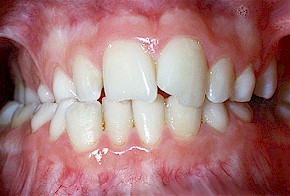

Zahnfehlstellung

Tiefbiss (tiefer Biss)

Die oberen Schneidezähne überlappen die unteren

Schneidezähne mehr als 3 mm und man sieht die unteren

Schneidezähne kaum noch [24].

Beim Tiefbiss überdecken die oberen Schneidezähne

die unteren Schneidezähne fast komplett.

Man sieht die unteren Schneidezähne kaum noch (Foto

von Praxis Dr. Kuster).